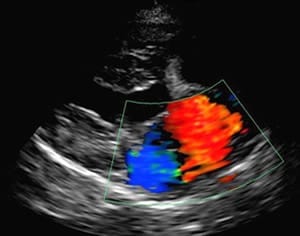

超音波検査

超音波診断装置を使用して心臓の壁の厚さ、内腔の大きさ、内部を流れる異常な血流を検出します。